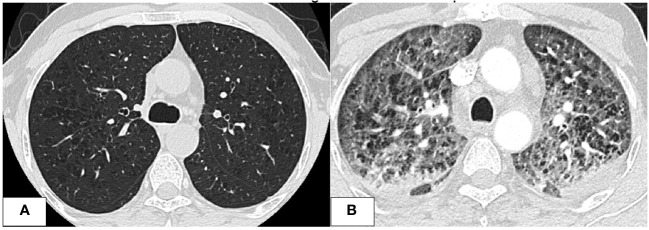

Further investigations with imaging of the chest and paranasal sinuses with computed tomography (CT) were done; the chest CT showed multiple bilateral peri-broncho-vascular rounded central consolidative nodules and cavities representing an inflammatory/infectious process. He was started on Posaconazole. Bronchoscopy and bronchoalveolar lavage (BAL) were negative for infections, including aspergillus galactomannan antigen. However, he was continued on antifungal treatment for six weeks as he was labeled to have a probable invasive fungal infection. While on antifungal treatment, he was started on cycle 1 of azacitidine and venetoclax and achieved remission, and a repeat CT chest after completion of antifungal therapy showed resolution of the previous findings. He initially refused to receive further cycles; however, after three months, he had a relapse with 80% circulating blasts, so he was restarted on azacitidine and venetoclax. On day 2 of the second cycle of azacitidine and venetoclax, he developed a fever and tachypnea. Chest examination was normal, and chest x-ray did not reveal any significant abnormality and had neutropenia on CBC. A microbiological work-up was sent, and he was started on empirical antibiotics with meropenem as he was kept on prophylactic levofloxacin, according to the institute’s febrile neutropenia protocol. Despite empirical antibiotics, he continued to have fever and worsening symptoms. Antimicrobial therapy was upgraded with antifungal treatment, vancomycin, and later sulfamethoxazole-trimethoprim, yet there was no significant improvement. CT chest showed bilateral diffuse ground-glass opacities, smooth interlobular septal thickening, severe emphysematous changes, and small bilateral pleural effusions with no evidence of pulmonary embolism. The patient was kept on empirical antibiotics and completed seven days of azacitidine. On day 11, he became more tachypneic and hypoxic and was transferred to the intensive care unit (ICU) and was started on oxygen therapy with a high-flow nasal cannula. He continued empirical antimicrobial therapy despite all infectious work-ups returning negative (see T1). A bronchoscopy with bronchoalveolar lavage was done and was negative for malignant cells and infectious causes. BAL fluid was bloody with 24,500 x 106/L of RBCs. He was started on Methylprednisolone 40 mg IV BID for five days for possible drug-induced pneumonitis while continuing antibiotics. He improved clinically, was weaned off oxygen therapy, and was discharged from the hospital. He was re-admitted for the third cycle of azacitidine and venetoclax. On day 5 of cycle 3 of azacitidine, he developed a fever, shortness of breath, and hypoxia. Chest x-ray showed bilateral diffuse reticulonodular opacities. An infectious work-up was sent, and he was started on empirical antimicrobial therapy. CT chest showed diffuse bilateral ground glass densities with smooth interlobular septal thickening, centrilobular nodules, and right upper lobe ground glass opacity with focal subpleural infiltrate (f1). Azacitidine-induced pneumonitis was our top differential diagnosis as the symptoms reoccurred with rechallenging with azacitidine, and the Naranjo score was 8, which makes the diagnosis probable (T2). Azacitidine was discontinued, and he was started on dexamethasone 4 mg IV BID for three days, then tapered down and changed to prednisone orally, which was stopped after six weeks with clinical and radiological improvement. Treatment of his AML was changed to cladribine, low-dose cytarabine with venetoclax with no similar lung toxicity. The patient achieved complete remission, however he refused further treatment, relapsed 4 months later and died within a month of his relapse.